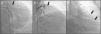

A 64-year-old Caucasian male with a history of coronary artery bypass grafting (CABG) [internal mammary artery (IMA) graft to the left anterior descending artery (LAD) and saphenous vein graft to right posterior descending artery (PDA)], presented with stable angina with a positive treadmill exercise test. Coronary angiography (CAG) documented occlusion of both middle LAD and IMA grafts (Figure 1, panel A); no significant lesions were found in the circumflex artery or the saphenous vein graft. The CAG performed prior to surgery is shown in Figure 2.